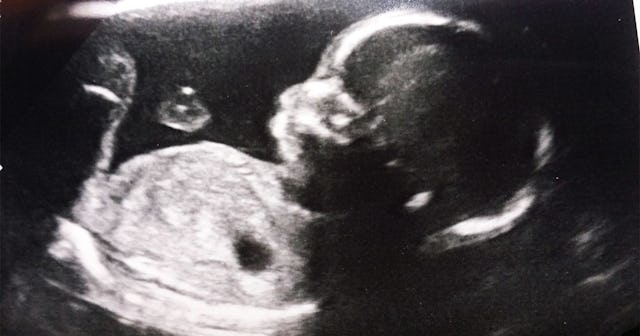

The first proven case of COVID-19 being transmitted in utero occurred with a mother and baby in Paris, doctors are reporting. The newborn baby boy developed inflammation in the brain within days of being born, which was brought on after the virus crossed the barrier of the placenta and established an infection before birth. Both the mother and the baby have since recovered, but this is still very grave news for pregnant persons all over the world.